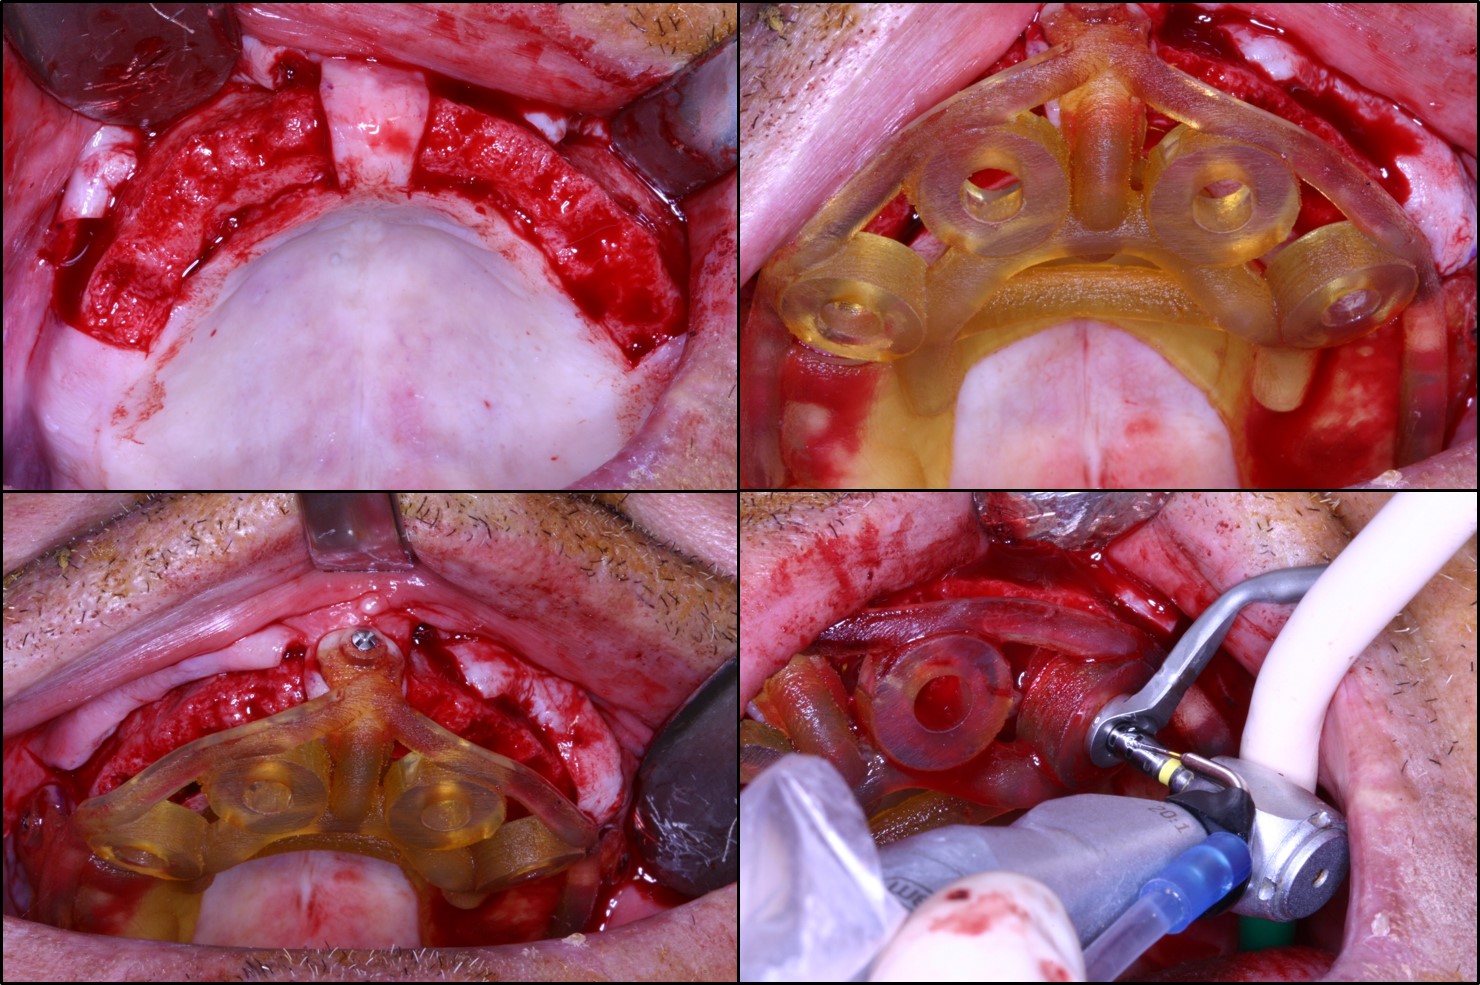

Σε περιστατικά ολικής αποκατάστασης με οδοντικά εμφυτεύματα, σημαντική βοήθεια προσφέρουν πλέον οι ηλεκτρονικοί υπολογιστές, η εφαρμογή των οποίων επιτρέπει το σχεδιασμό της τελικής προσθετικής αποκατάστασης σε εικονικό περιβάλλον και τη μελέτη του αριθμού, της θέσης και της κλίσης των οδοντικών εμφυτευμάτων, ώστε αυτά να υποστηρίζουν με τον ιδανικό τρόπο τη μελλοντική προσθετική εργασία ανάλογα με τις ανατομικές συνθήκες που υφίστανται σε κάθε ασθενή (Εικόνα 7).

Ακολούθως εκτυπώνεται από 3D printer ένας χειρουργικός οδηγός ακριβείας, ο οποίος χρησιμοποιείται κατά τη διάρκεια της επέμβασης και καθοδηγεί το χειρουργό στην τοποθέτηση των οδοντικών εμφυτευμάτων (Εικόνα 8). Σε τέτοιες περιπτώσεις συνήθως ακολουθεί άμεση φόρτιση των οδοντικών εμφυτευμάτων, δηλαδή αμέσως μετά τη χειρουργική επέμβαση ο οδοντίατρος παραδίδει στον ασθενή μία προσωρινή ακίνητη προσθετική εργασία, η οποία καλύπτει τις αισθητικές και λειτουργικές του ανάγκες μέχρι βιολογικά να οστεοενσωματωθούν τα οδοντικά εμφυτεύματα και να ακολουθήσει η διαδικασία της τελικής προσθετικής αποκατάστασης (Εικόνα 9). Η όλη διαδικασία μειώνει σημαντικά το συνολικό χρόνο της αποκατάστασης και αυξάνει κατακόρυφα την αποδοχή της θεραπείας από πλευράς ασθενών.